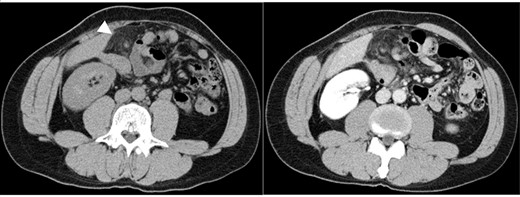

The patient’s body mass index was 23.5. On physical examination, the patient had a pulse of 73 beats/min, blood pressure of 133/82 mm Hg and temperature of 37.4°C.Rebound tenderness and abdominal guarding were recognized in the upper quadrant. The patient had no associated nausea or vomiting. Blood tests showed elevated C-reactive protein (CRP) and white blood cell (WBC) count (6.1 mg/dl and 9300/mm3, respectively). Plain abdominal computed tomography (CT) showed a nodular mass and high-density lesions in the fat tissue near the hepatic flexure of the ascending colon (Fig. 1). In contrast-enhanced CT, the nodular mass and torsion were unclear. Based on the CT scans and the patient’s severe clinical symptoms, acute appendicitis was considered doubtful; rather, we suspected acute abdominal conditions such as internal hernia, omental torsion, epiploic appendagitis, diverticulitis or omental infarction. Given the severity of the patient’s symptoms, observable deterioration and lack of a clear diagnosis, we performed exploratory laparoscopy.

Abdominal CT images: nodular mass and high-density lesions in the fat tissue near the hepatic flexure of the ascending colon are evident (white arrow).